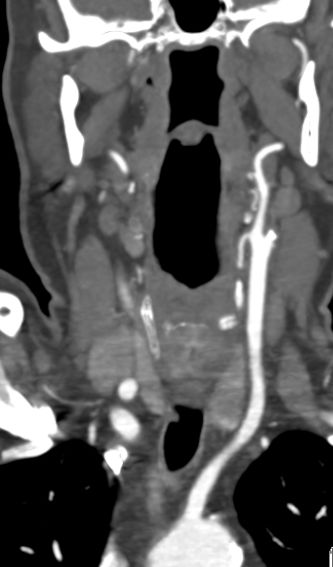

ACI-Verschluß 63-jährige Frau, die wegen TIA eingeliefert wurde. Daraus entwickelte sich eine komplette Halbseitensymptomatik. Das CT zeigt einen Abgangsverschluss der linke ACI.

CT-Angio

Gut markierter Media-Infarkt